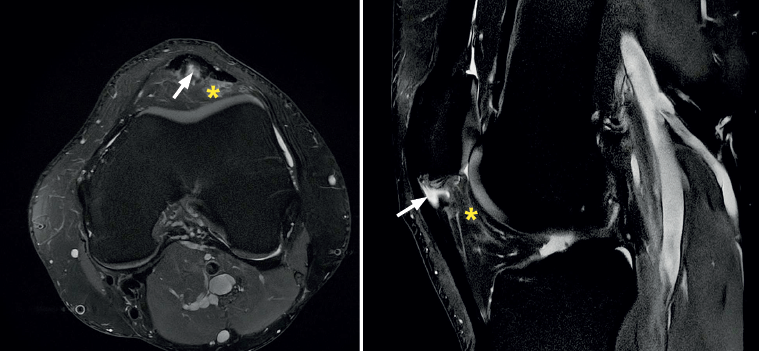

The most common MRI finding is increased signal intensity in the lower pole of the patella, with local widening of the affected zone of the tendon (Figure 7)(14,25). The most evident advantage of MRI with respect to ultrasound is its capacity to visualise associated lesions in the joint and cartilage, as well as the presence of bone edema and involvement of Hoffa's fat pad (Figure 7). As clear disadvantages, mention must be made of the high cost of the technique and the impossibility of performing exploration in motion or at different angles of flexion of the knee.

Figure 7. Magnetic resonance imaging view showing alteration of the proximal patellar tendon with thickening and edema (white arrow), in a segment measuring 1.5 cm in length. Marked edema of adjacent Hoffa's fat pad (asterisk).